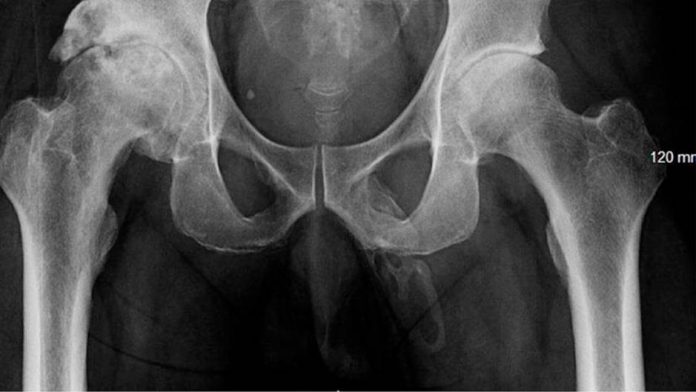

The x-ray images show that in the Penis bone-like calcium deposits are located. Calcium crystals deposited in the tissue and a Plaque-like structure is formed. In fact, the man is to have pain in his Penis.